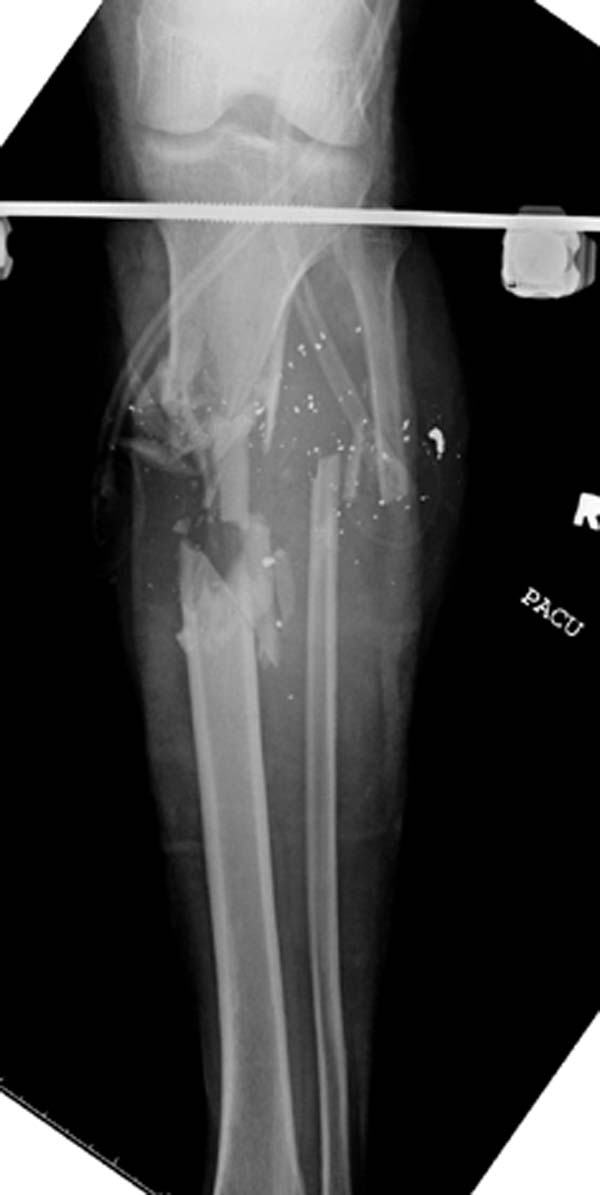

Имя     : 2 gsw tibia lat injury.jpg

Url     : http://weborto.net:8080/pipermail/ortho/attachments/20150717/eea7e369/attachment-0015.jpg